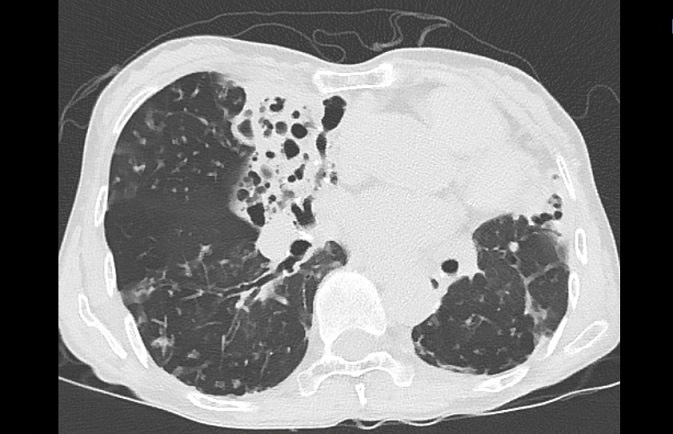

기관지확장증의 CT 사진

비결핵항산균에 감염된 폐사진